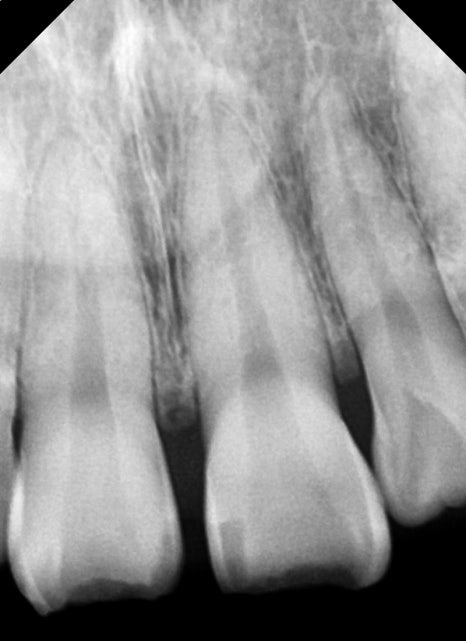

첫 번째 환자분과 다르게 이분은 치아의 동요도도 관찰되었기 때문에 사진처럼 치아를 고정할 수 있는 임시 치간 고정술을 진행했습니다.

흔들리는 치아는 정도에 따라 고정 장치의 유지 기간이 좀 다를 수 있지만 일반적으로 2~4주 이상은 권하고 있지 않습니다.

엑스레이 내에서 추가적인 치아 파절의 흔적은 보이지 않아 치아의 흔들림을 고정시킨 후 치아 파절 부위나 치아 신경의 생활력을 평가하기 위해 2주 후 체크를 해봤습니다.